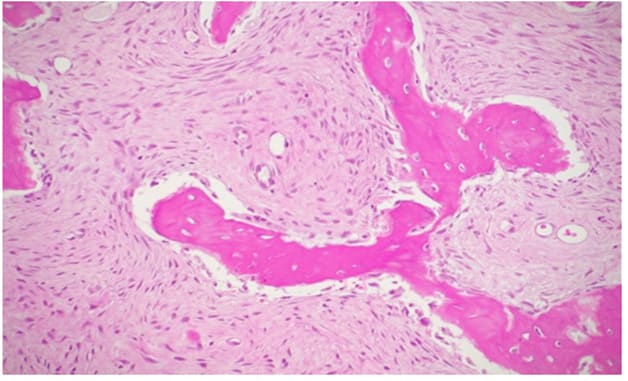

In both cases, histopathological examination revealed osseous tissue characterized by immature bony trabeculae with irregular shapes and sizes, thin and disconnected from each other, surrounded by a fibroblastic stroma, without evidence of osteoblastic activity. At the periphery of the biopsy specimen, the fibro-osseous tissue merged with bone without encapsulation or a demarcation line. This histological pattern is consistent with a diagnosis of fibrous dysplasia. Genetic testing for GNAS gene mutations was not performed because this investigation has a low statistical sensitivity and is useful for uncertain histopathological diagnoses.

Histopathological Features:

Figure 12: H&E 250X2, areas with predominant fibrous component.